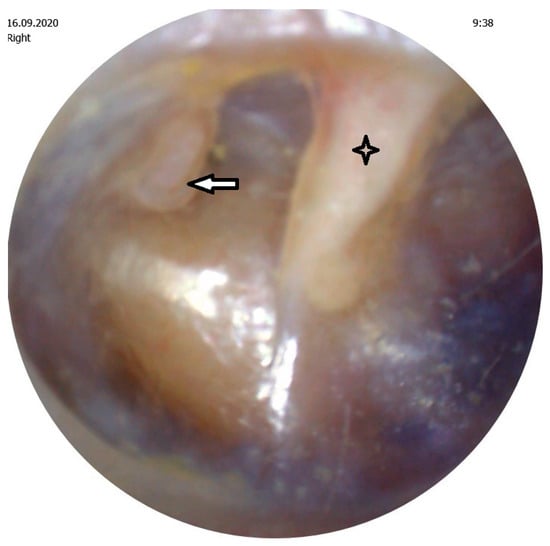

Malleus,

Erosion of the incudostapedial joint.